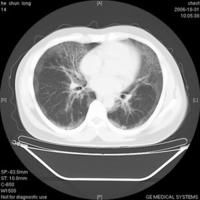

肺泡蛋白質(zhì)沉積癥(pulmonary alveolar proteinosis,簡(jiǎn)稱(chēng)PAP),又稱(chēng)Rosen-Castle-man-Liebow綜合征。以肺泡和細(xì)支氣管腔內(nèi)充滿(mǎn)PAS染色陽(yáng)性,來(lái)自肺的富磷脂蛋白質(zhì)物質(zhì)為其特征。好發(fā)于青中年,男性發(fā)病約3倍于女性。病因未明,可能與免疫功能障礙(如胸腺萎縮、免疫缺損、淋巴細(xì)胞減少等)有關(guān)。粉塵尤以接觸矽塵的動(dòng)物可引起PAP,故認(rèn)為可能是對(duì)某些刺激物的非特異反應(yīng),導(dǎo)致肺泡巨噬細(xì)胞分解,產(chǎn)生PAS陽(yáng)性蛋白質(zhì)。